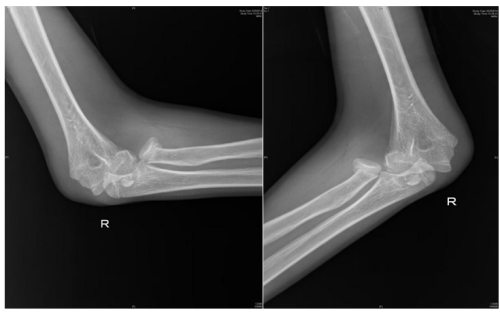

术前检查提示桡骨头骨折,肱骨远端骨折,肘关节脱位

近日,13岁的邓佑(化名)在放学途中,一边看手机一边走路,未留意前方障碍,整个人猛地撞上了护栏,在倒地的瞬间,他用右手撑地,随即感到一阵钻心的剧痛从肘部爆发开来,被紧急送往91短视频 (南华大学附属长沙中心医院)手足显微外科就诊。经系统检查,被诊断为:右桡骨头骨折、肱骨内上髁骨折、右肘关节脱位。

“患者入院后,我们紧急行右肘关节脱位复位,肿胀消退后为其设计了尽可能微创的手术方案:右桡骨头骨折闭合复位弹性髓内针内固定+肱骨内上髁骨折切开复位内固定,手术顺利。术后患者恢复良好,即将出院。”据该院手足显微外科主任、副主任医师蒋亮东介绍,医院经常接诊因低头看手机导致意外受伤的患者。其中,桡骨头骨折在青少年人群中尤为常见,它通常是由于在摔倒时手掌撑地,间接暴力传导至肘部而发生的骨折。